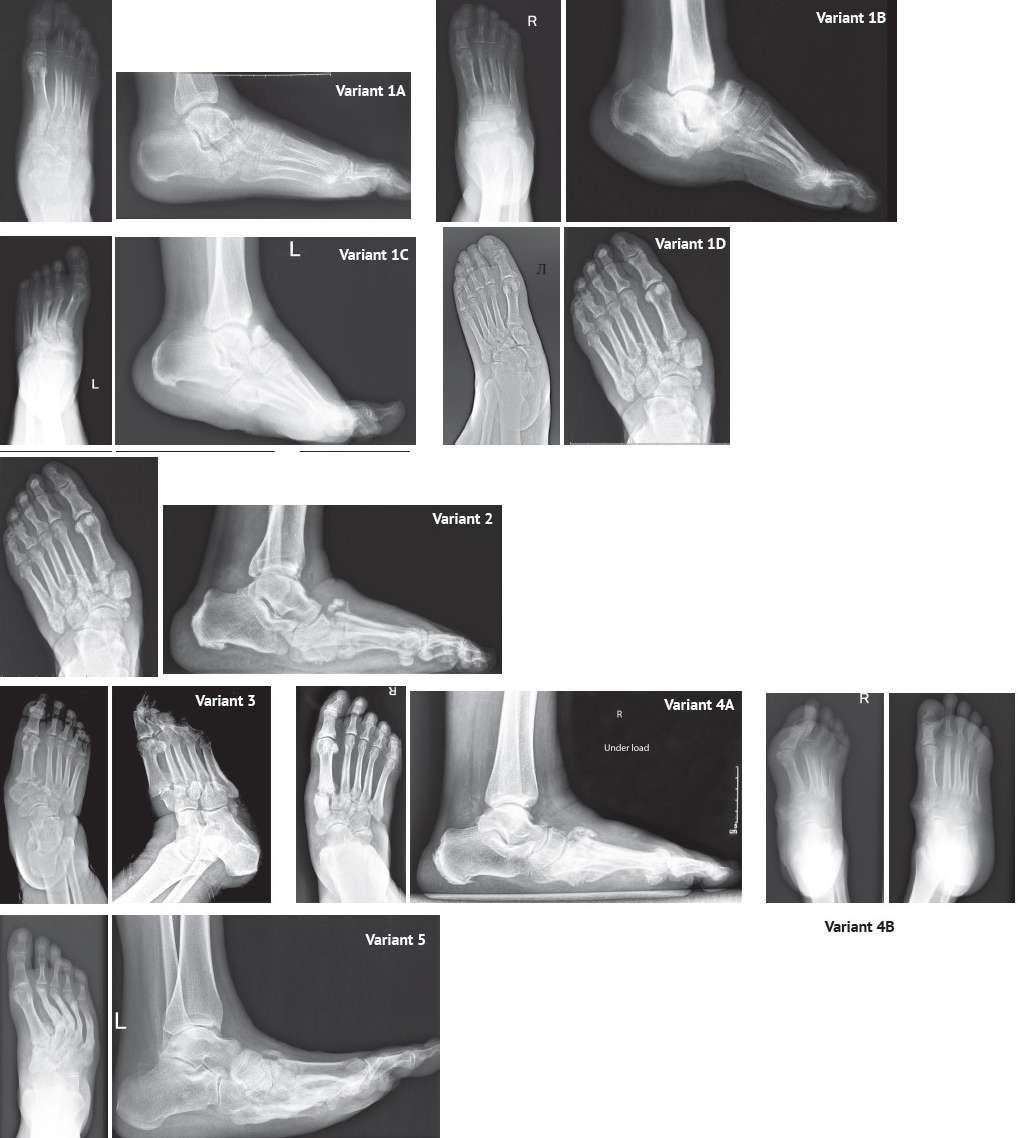

The deformity variants are illustrated in X-rays (Figure 2).

Figure 2. Deformity variants

Results. The following types of lesions are identified. 1A — involvement of the navicular bone and talar head with the preservation of the lateral column anatomy. 1B — simultaneous involvement of the talonavicular and calcaneocuboid joints. 1C — subluxation or dislocation of the talonavicular joint with transition to the lateral parts of the tarsometatarsal joint with plantar dislocation of the cuboid bone and preservation of anatomical integrity in the calcaneocuboid joint. 1D — complete displacement of the navicular bone with the dislocation of the talonavicular, naviculocuneiform and tarsometatarsal joints. 2 — deformation (subluxation, dislocation, fracture-dislocation) of the naviculocuneiform joint, with involvement of the lateral column in the metatarsocuboid joint and flattening of the medial column. 3 — isolated involvement of the Lisfranc joint. 4A — isolated involvement (subluxation or dislocation) of the first cuneometatarsal joint without visible deformity in the affected area. 4B — dislocation of the medial naviculocuneiform and medial cuneometatarsal joints with the displacement of the medial cuneiform bone relative to the other foot bones. 5 — varus deformity of the foot with fractures of the metatarsal bones.

Based on the analysis of X-rays, nine primary types of typical midfoot bone displacements were identified, which in many aspects differ from those described in existing classification systems. The variants were numbered from 1 to 5, proceeding from the hindfoot toward the forefoot. In addition to the main numbering, two variants (1 and 4) were subdivided into subtypes based on the specific features of involvement within the same type. The displacement characteristics for each variant are descri-bed below.

Variant 1. Deformity (subluxation, dislocation, or fracture-dislocation) of the Chopart joint. This variant includes subtypes:

Variant 1А. Involvement of the navicular bone and talar head with the preservation of the lateral column anatomy. Typical features of this subtype include:

- defect of the talar head and/or navicular bone;

- preservation of an intact lateral column;

- no visually significant foot deformity.

Variant 1B. Simultaneous involvement of the talonavicular and calcaneocuboid joints (dorsal dislocation or subluxation of the navicular and cuboid bones). Typical features of this subtype include:

- dorsal displacement of the midfoot bones (navicular and cuboid) relative to the hindfoot bones (talus and calcaneus);

- preservation of an intact tarsometatarsal (Lisfranc) joint;

- equinus positioning of the talus and calcaneus bones without disruption of the subtalar joint alignment.

Variant 1C. Simultaneous involvement of the talonavicular and tarsometatarsal joints (dorsal dislocation or subluxation of the navicular and cuboid bones). This subtype is characterized by:

- dorsal displacement of the navicular bone along with the midfoot and forefoot bones;

- plantar dislocation of the cuboid bone at the cuboid-metatarsal joint;

- equinus positioning of the hindfoot (talus, calcaneus, and cuboid bones).

Variant 1D. Total displacement of the navicular bone with dislocation at the talonavicular and naviculocuneiform joints. This subtype is characterized by:

- plantar and/or medial dislocation of the navicular bone;

- dorsal dislocation of the medial cuneiform bone;

- dorsolateral displacement of the metatarsal bones;

- plantar displacement of the cuboid bone at the cuboid-metatarsal joint;

- dislocation of the intermediate and lateral cuneiform bones either in plantar direction together with the cuboid bone or dorsally along with the metatarsals;

- supinated positioning of the metatarsal bones;

- equinus positioning of the hindfoot.

Variant 2. Deformity (subluxation, dislocation, or fracture-dislocation) of the naviculocuneiform joint, possibly involving the lateral column at the cuboid-metatarsal joint, with progressive deformity and flattening of the medial column. This subtype is characterized by:

- destruction within the naviculocuneiform joint with preserved anatomical alignment of the Chopart joint;

- possible involvement of the lateral column at the tarsometatarsal joint;

Variant 3. Deformity (subluxation, disloca-tion, or fracture-dislocation) of the Lisfranc joint. This subtype is characterized by:

- subluxation of the metatarsal bones in the Lisfranc joint with valgus positioning and abduction;

- prolapse of the foot with plantar displacement;

- possible destructive changes in the Lisfranc joint;

- development or worsening of pre-existing valgus foot deformity;

- depending on the severity of destruction, possible plantar dislocation of the cuboid bone in the cuboid-metatarsal joint.

Variant 4. Isolated deformity (subluxation, dislocation, or fracture-dislocation) of the medial column involving the medial cuneometatarsal joint. This variant includes two subtypes.

Variant 4A. Isolated involvement (subluxa-tion or dislocation) of the first cuneometatarsal joint without visible deformity in the affected area. This subtype is typically characterized by the elevation of the head of the first metatarsal bone.

Variant 4B. Dislocation of both the medial naviculocuneiform and medial cuneometatarsal joints with the displacement of the medial cuneiform relative to the other foot bones, potentially accompanied by ulceration in the area of the dislocated bone.

Variant 5. Varus deformity of the foot with fractures of the metatarsal bases and possible impaction of bones in the medial column. This variant is characterized by the following features:

- – initial pes cavovarus deformity, which under conditions of neuropathic arthropathy may lead to fractures of the metatarsal bases at peak load zones, further aggravating forefoot adduction and supination, with eventual involvement of medial column bone destruction at later stages;

- – development of ulcerative defects along the lateral edge of the plantar surface of the foot.